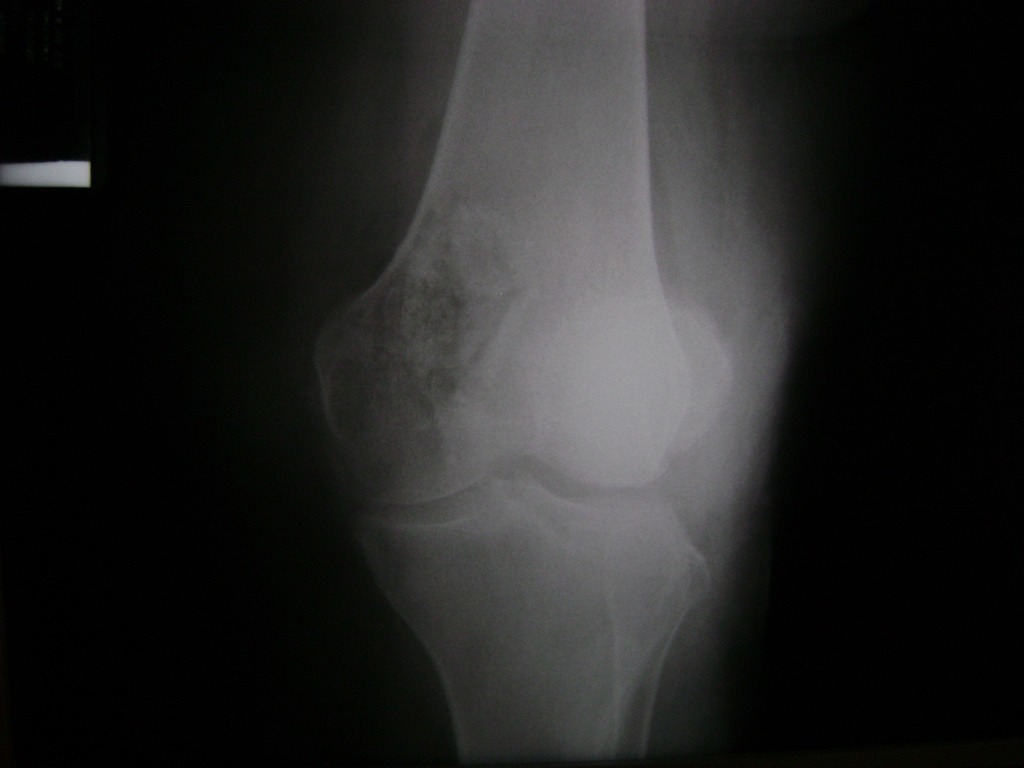

Fémur - Rodilla

La artroscopia de rodilla es un cirugía en el cual la estructura interna de la articulación es examinada ya sea para realizar un diagnostico o para realizar un tratamiento, este procedimiento se realiza utilizando un instrumento parecido a un pequeño tubo llamado artroscopio.